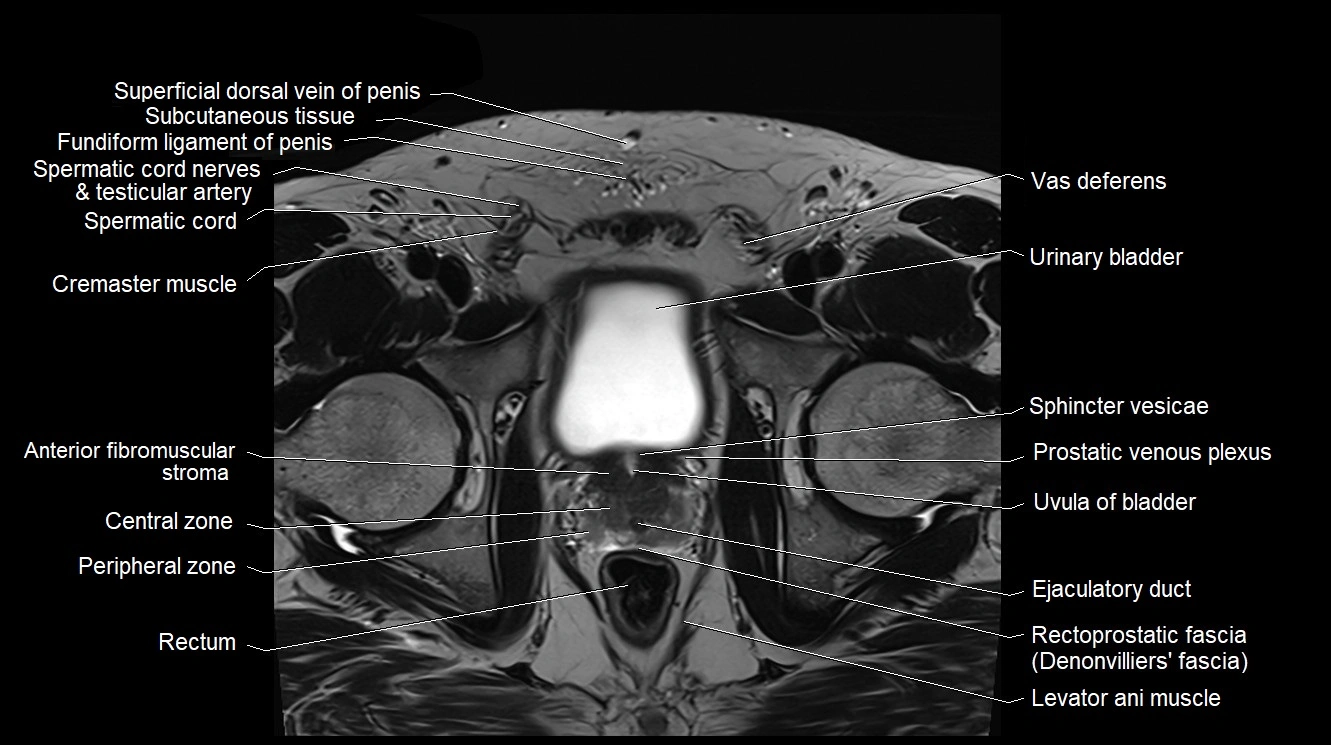

MRI image